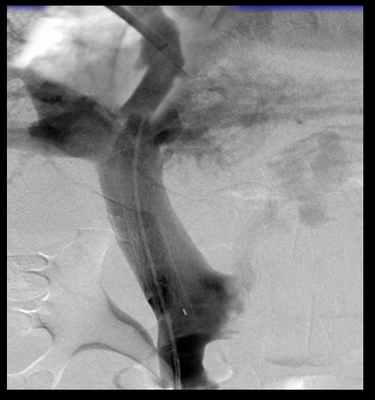

- Прямая портография (чрезпеченочное введение катетера и контрастирование воротной системы) - заключительный метод диагностики перед вмешательством.

После определения целевой воротной вены через катетер в печеночной вене проводится пункция специальной иглой. Проведя последнюю в воротную вену через нее устанавливают проводник и проводят катетер. Проводится контрастирование воротной системы через яремный катетер и замеряется давление в воротной системе.

При выполнении TIPS крайне важны правильная регистрация и интерпретация показателей венозного давления. Измерение ГДПВ обычно проводится под седацией и местной анестезией. Интродьюсер устанавливается обычно в правую яремную вену пункционно по методике Сельдингера. Реже используются бедренный или кубитальный доступы. Катетер с баллончиком на рабочей части (Swan-Ganz или Goodale Lubin) диаметром 7-Fr под рентген-телевизионным контролем проводится и «заякоривается» в печеночной вене на глубине 3–4 см от устья печеночной вены. Измеряется СДПВ. После стабилизации показателей СДПВ и подтверждения герметичности окклюзии просвета печеночной вены баллоном трехкратно регистрируются показатели ДЗПВ. Учитывается их среднее значение, причем разница всех трех измерений не должна превышать 1 мм рт. ст. При наличии показаний к шунтированию проводник из печеночных вен через паренхиму печени низводится в одну из ветвей воротной вены. Проводятся канюляция воротной вены и портография. Устанавливается саморасширяющийся стент.